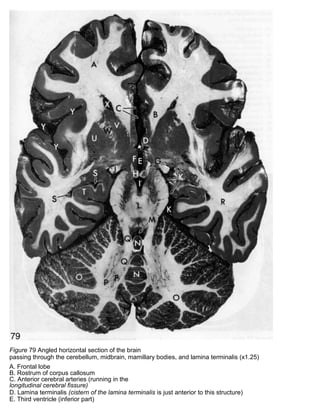

Figure 79 Angled horizontal section of the brain

passing through the cerebellum, midbrain, mamillary bodies, and lamina terminalis (x1.25)

A. Frontal lobe

B. Rostrum of corpus callosum

C. Anterior cerebral arteries (running in the

longitudinal cerebral fissure)

D. Lamina terminalis (cistern of the lamina terminalis is just anterior to this structure)

E. Third ventricle (inferior part)

F. Hypothalamus

G. Column of fornix (entering mamillary body)

H. Mamillary body

I. Interpeduncular cistern

J. Optic tract

K. Ambient cistern

L. Midbrain

M. Fourth ventricle

N. Cerebellar vermis

o. Cerebellar hemisphere

P. Dentate nucleus of cerebellum

Q. Dentatorubrothalamic tract (leaving the dentate nucleus and ascending, via the superior cerebellar

peduncle, to the midbrain)

R. Temporal lobe

S. Inferior horn of lateral ventricle

T. Hippocampus

U. Putamen of lentiform nucleus

V. Head of caudate nucleus

W. Anterior limb of internal capsule

X. Tip of anterior horn of lateral ventricle

Y. Lateral sulcus (with branches of middle

cerebral artery in it)

Figure 79 Angledhorizontal section of the brain passing through the cerebellum, midbrain, mamillary bodies, and lamina terminalis (x1.25) A. Frontal lobe B. Rostrum of corpus callosum C. Anterior cerebral arteries (running in the longitudinal cerebral fissure) D. Lamina terminalis (cistern of the lamina terminalis is just anterior to this structure) E. Third ventricle (inferior part)

• 9.

F. Hypothalamus G. Columnof fornix (entering mamillary body) H. Mamillary body I. Interpeduncular cistern J. Optic tract K. Ambient cistern L. Midbrain M. Fourth ventricle N. Cerebellar vermis o. Cerebellar hemisphere P. Dentate nucleus of cerebellum Q. Dentatorubrothalamic tract (leaving the dentate nucleus and ascending, via the superior cerebellar peduncle, to the midbrain) R. Temporal lobe S. Inferior horn of lateral ventricle T. Hippocampus U. Putamen of lentiform nucleus V. Head of caudate nucleus W. Anterior limb of internal capsule X. Tip of anterior horn of lateral ventricle Y. Lateral sulcus (with branches of middle cerebral artery in it)